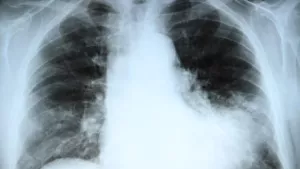

První kazuistika se týká úmrtí mladého muže s nemalobuněčným karcinomem plic metastazujícím do mozku. Soudní znalec byl osloven s tím, že péče o tohoto pacienta byla zanedbána – rodina si stěžovala na fakt, že onkologické onemocnění nebylo diagnostikováno při prvním pobytu ve zdravotnickém zařízení, kde byl nemocný vyšetřován pro rozpadovou dutinu v horním plicním laloku, v tu dobu měl akutní potíže. Byla mu nasazena antibiotika, po kterých došlo ke zmírnění obtíží, takže byl případ uzavřen jako pneumonie s rozpadem, a muž byl s léčbou odeslán do domácí péče. Doporučeno bylo CT vyšetření plic. To následně prokázalo tumor plic, který byl adekvátně diagnostikován a léčen, avšak neúspěšně.